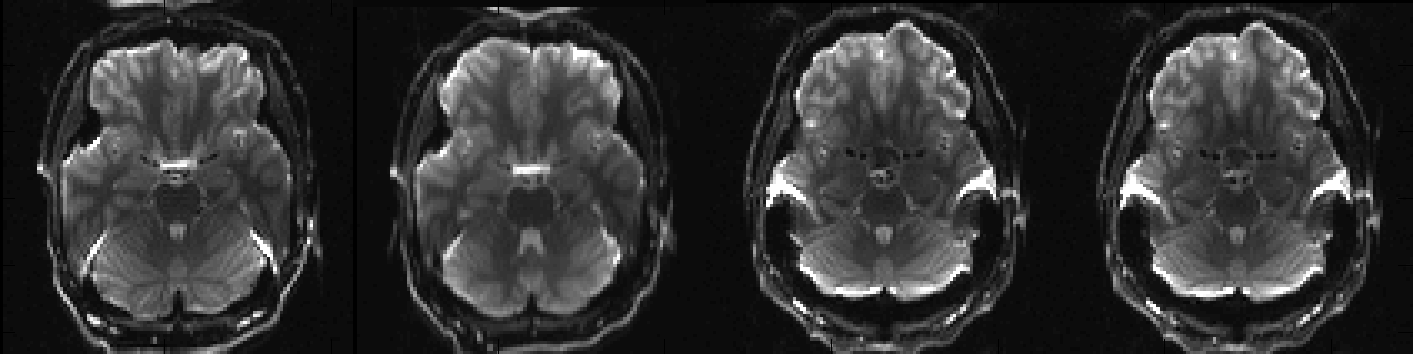

So, let us first take a look at my_unwarped_images.nii.gz to see if topup has done a decent job at correcting the distortions.

I think we can agree that that looks quite good and that we have no reason to think that topup ran into any problems. Let us now look at my_topup_results_movpar.txt to see if we were right in our suspicion that there had been some movement.